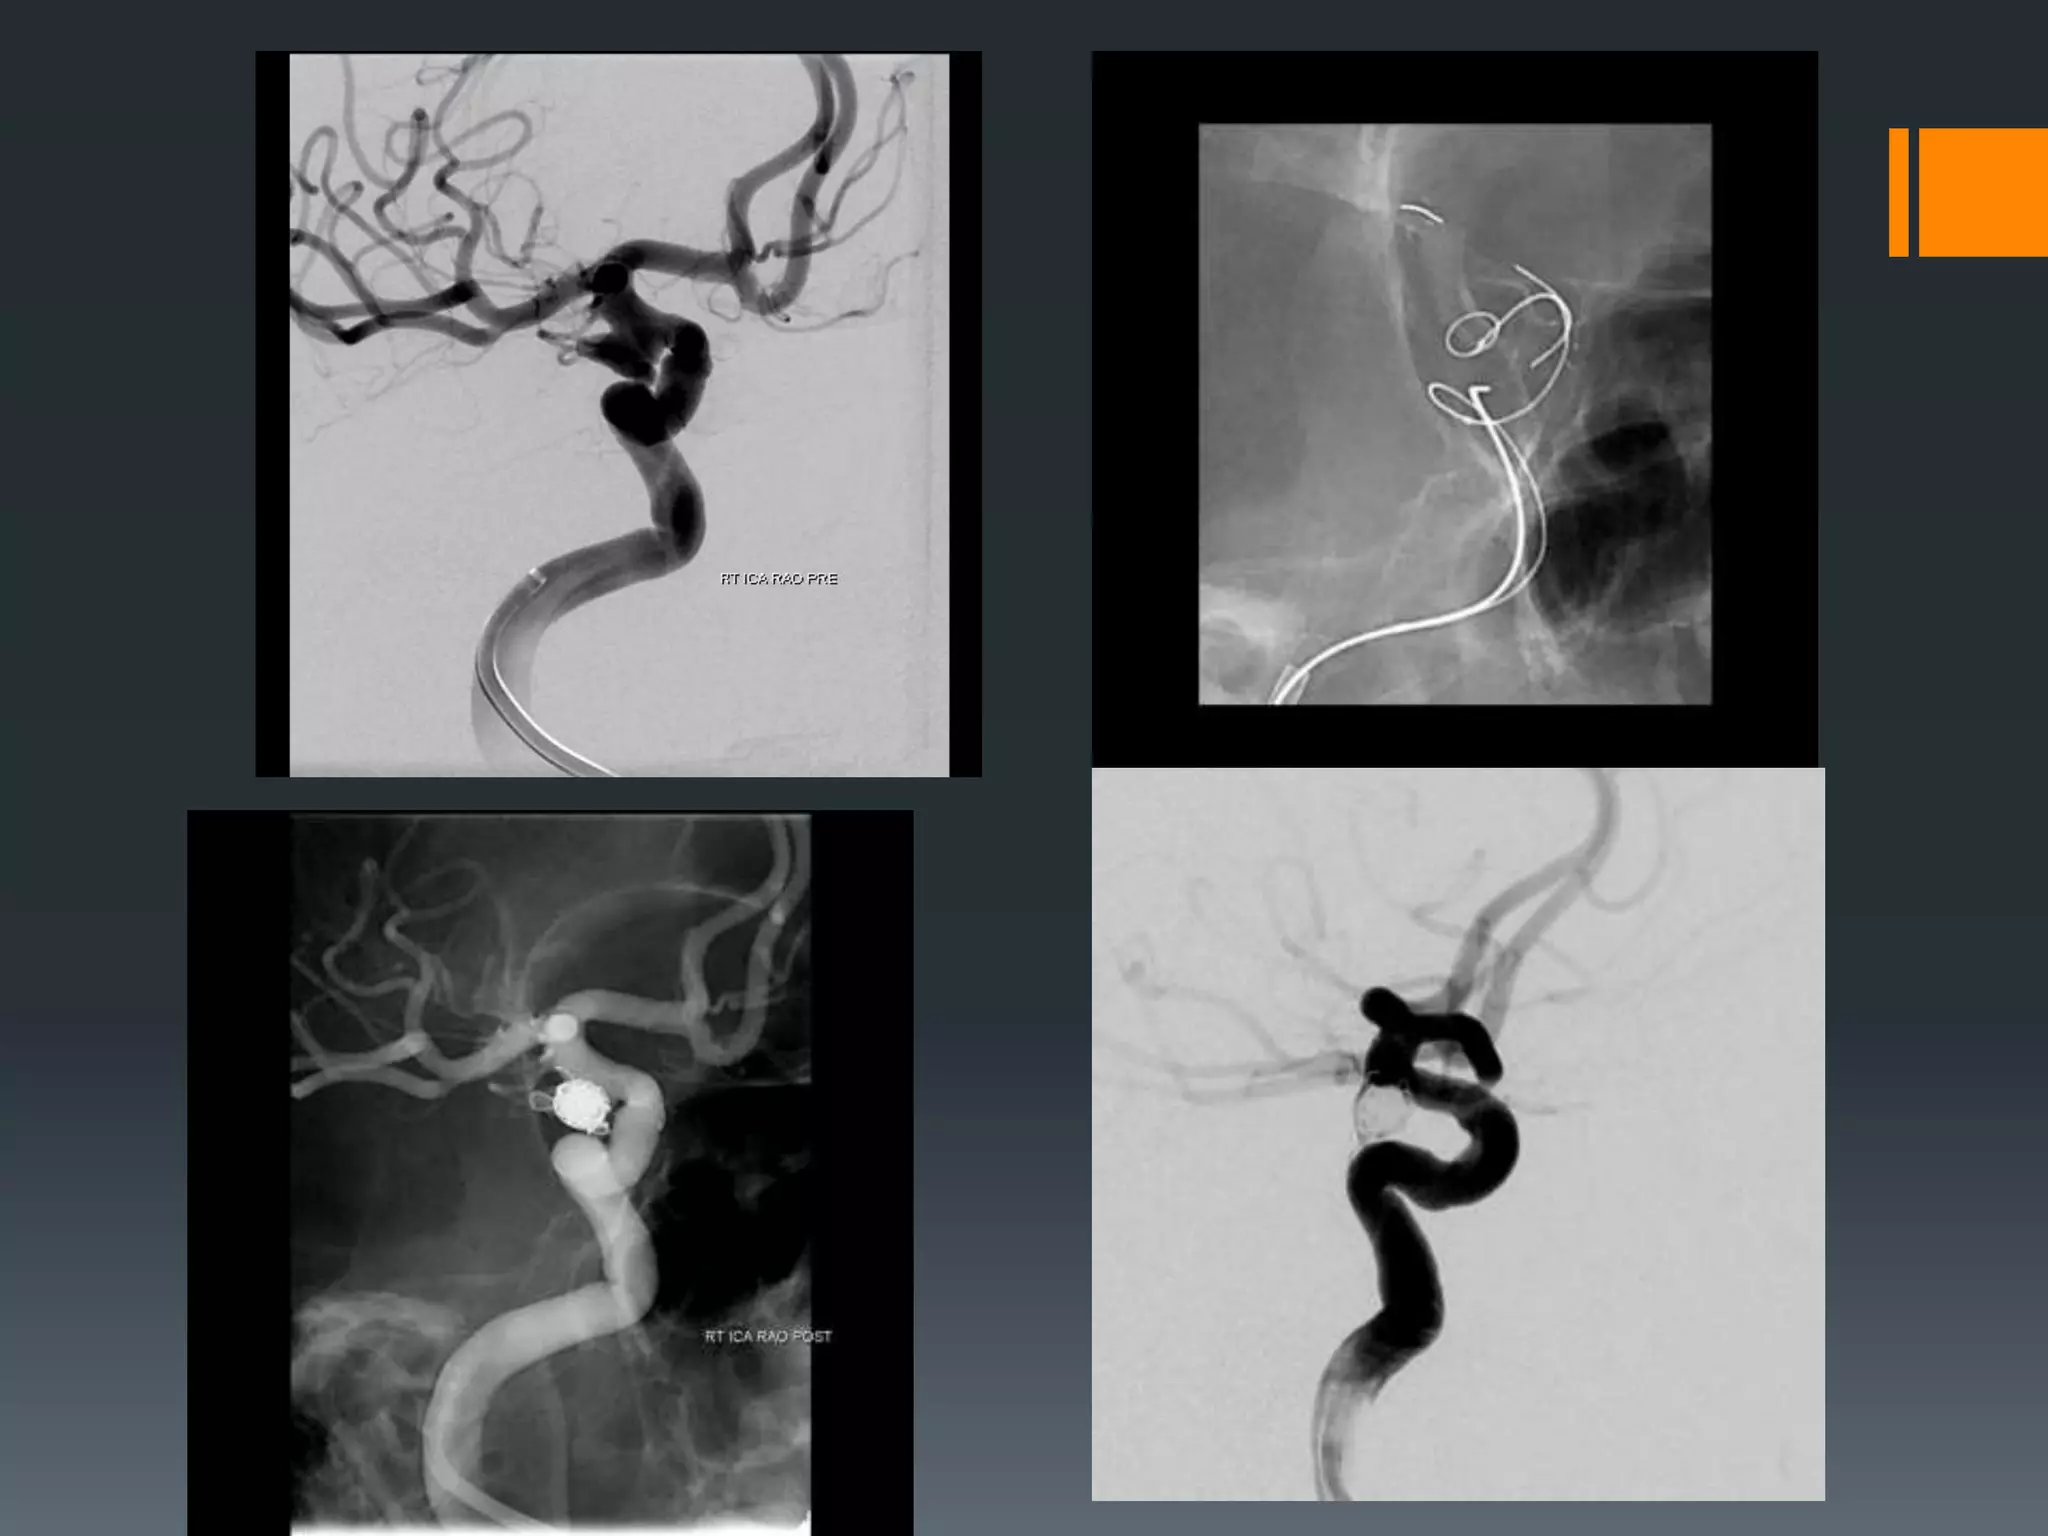

This document discusses tricks and techniques for difficult cannulations during neurointerventional procedures. It outlines strategies for accessing the aortic arch, internal carotid artery (ICA), and areas distal to aneurysms. Long sheaths, distal access catheters, and co-axial techniques are presented as options that have improved cannulation success. Guidance on sheath and catheter selection is provided for different vessel paths. The importance of catheter placement as high as possible in the ICA is emphasized. Reverse curve cannulations are also mentioned. Overall, the document stresses that careful cannulation is critical for procedural success and different strategies may be needed depending on the vessel target.